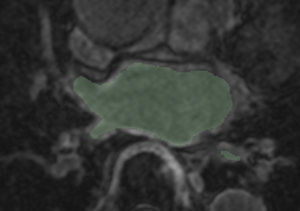

Example 1

Checker-filter: Pre and registered post LGE images Checker-filter: Pre and registered post LGE images Pre segmentation overlaid on registered post LGE Pre segmentation overlaid on registered post LGE

CARMA VecReg Seg1.png

CARMA VecReg Seg1-2.png